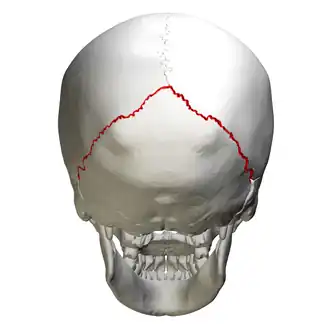

![]() Lambdoid suture, posterior view | |

The lambdoid suture, or lambdoidal suture, is a dense, fibrous connective tissue joint on the posterior aspect of the skull that connects the parietal bones with the occipital bone. It is continuous with the occipitomastoid suture.

The lambdoid suture is between the paired parietal bones and the occipital bone of the skull. It runs from the asterion on each side.

The lambdoid suture is named due to its uppercase lambda-like shape.

Animation. Lambdoid suture shown in red. -